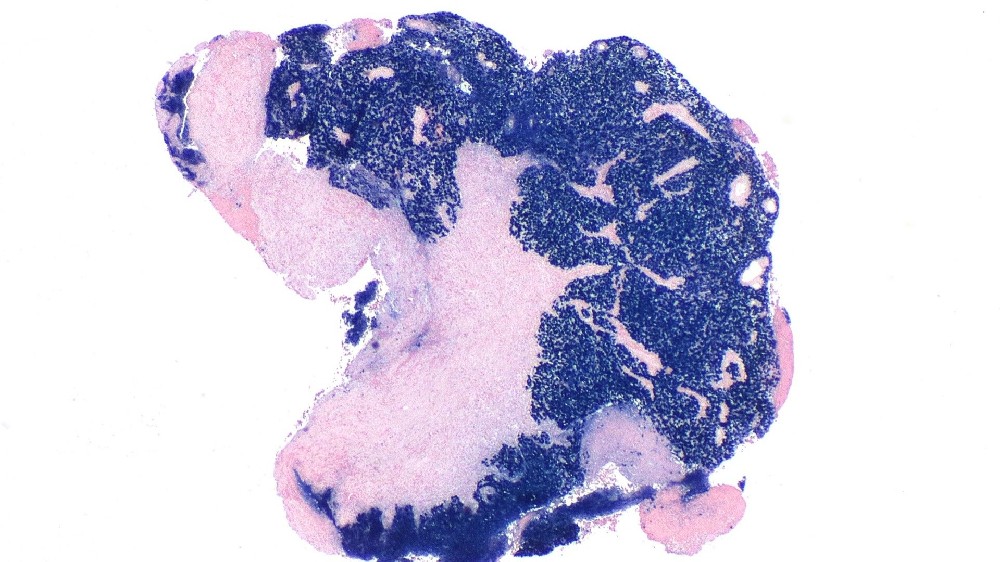

鼻咽癌 (Nasopharyngeal Carcinoma)鼻咽癌又簡稱為 NPC,是一種起源於鼻咽上皮內膜的惡性腫瘤,鼻咽上皮內膜是位於鼻子後面的喉嚨上半部。與一般頭頸部癌症不同的是,鼻咽癌在全世界相對不常見,但在東南亞地區,尤其是香港、中國大陸和亞洲鄰近地區的人口中,鼻咽癌的發病率卻高得不成比例。

了解鼻咽癌 (Nasopharyngeal Carcinoma) 需要深入瞭解其生物機制。從細胞層面來看,鼻咽癌起源於鼻咽上皮細胞的惡性轉變和不受控制的增生。在癌症中,鼻咽癌與 Epstein-Barr 病毒 (EBV) 感染有極高的關聯性,對於腫瘤的發展和惡性潛力有顯著的影響。

鼻咽癌 (Nasopharyngeal Carcinoma) 涉及快速且異常的細胞增生,通常是透過 EBV 感染途徑的病毒基因干擾所促成。